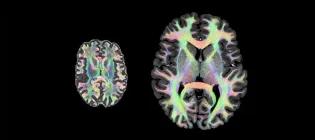

Over 1,200 staff and students collaborate across our core research areas, bringing together expertise that spans the body and life course. As part of driving progress in our core research areas, we host several leading research centres and house state-of-the-art technologies, which you can explore on this page. Want an introduction to our research first? Visit our Research page Explore the centres and units within our institute Anne Rowling Regenerative Neurology Clinic A globally leading, patient-centred, integrated care-research facility. The Clinic seamlessly integrates the best NHS health care with the best University health research, as key to discovering and trialling new treatments for neurological conditions. Euan MacDonald Centre for Motor Neuron Disease Research Pioneering vital research into motor neuron disease and unitiing over 300 scientists, doctors and healthcare professionals across Scotland, this centre is home to Europe’s largest clinical drugs trial for MND, MND-SMART. Jennifer Brown Research Laboratory A group working to improve understanding of what causes early labour, how we can develop treatments to prevent it and how we can better help newborn babies in those first crucial hours and days after birth. Muir Maxwell Epilepsy Centre A centre dedicated to investigating the causes of childhood-onset epilepsy. Simons Initiative for the Developing Brain Discovering the biological mechanisms underlying neurodevelopmental disorders - a research centre bringing together research groups across multiple sites. UKRI Mental Health Platform A network of researchers with the shared aim of accelerating research into severe mental illness and improving the diagnosis and treatment of those affected. British Heart Foundation Centre of Research Excellence A world-leading centre of excellence working to improve lives for people with cardiovascular, neurovascular, or metabolic health conditions. Edinburgh Clinical Research Facility State of the art facilities to support multidisciplinary clinical research locally, nationally and internationally. MRC/BHF Centre of Research Excellence in Advanced Cardiac Therapies (REACT) REACT unites academic, healthcare, industry and public partners to develop innovative DNA and RNA-based therapies capable of regenerating injured hearts and reversing established damage. It is co-led by King’s College London, the University of Edinburgh and the University of Oxford. Patrick Wild Centre A research centre that aims to better understand genetic conditions affecting brain development, and to improve the care and treatment available for people with these conditions. UK Dementia Research Institute at Edinburgh A centre of excellence that aims to elucidate the interactions within and between the brain vasculature, neurons, macroglia and microglia which control the trajectory of neurodegenerative disorders leading to dementia, and exploit this knowledge for therapeutic benefit. Centre for Pesticide Suicide Prevention A research and policy initiative working to reduce the number of pesticide suicides worldwide. Edinburgh Imaging World class imaging for research and diagnostic needs, working with academic researchers, NHS clinicians and commercial imaging organisations, including biotech, pharmaceutical & private medical industries. MS Society Edinburgh Centre for MS Research A multidisciplinary centre-without-walls funded by the MS Society, dedicated to laboratory, translational and clinical research into multiple sclerosis. Row Fogo Centre for Research into Ageing and the Brain Researchers working together to improve the understanding of how blood vessel diseases can damage the brain, leading to stroke, cognitive decline, dementia and mobility problems. UKRI Hub for Metabolic Psychiatry Part of the Mental Health Platform, this Hub brings together six interdisciplinary workstreams operating in concert to advance our understanding of the connection between metabolic and mental health. This article was published on 2026-03-17